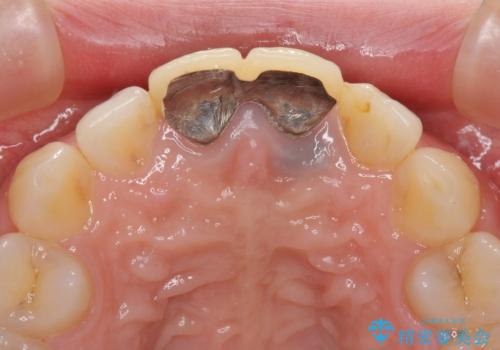

- 前歯のクラウンが着色により不自然な色となっていることを気にして来院された患者様です。

クラウンと歯の縁も合っておらず、汚れが溜まりやすい環境であったため、前歯2歯のクラウンをオールセラミッククラウンにて再補綴することとしました。